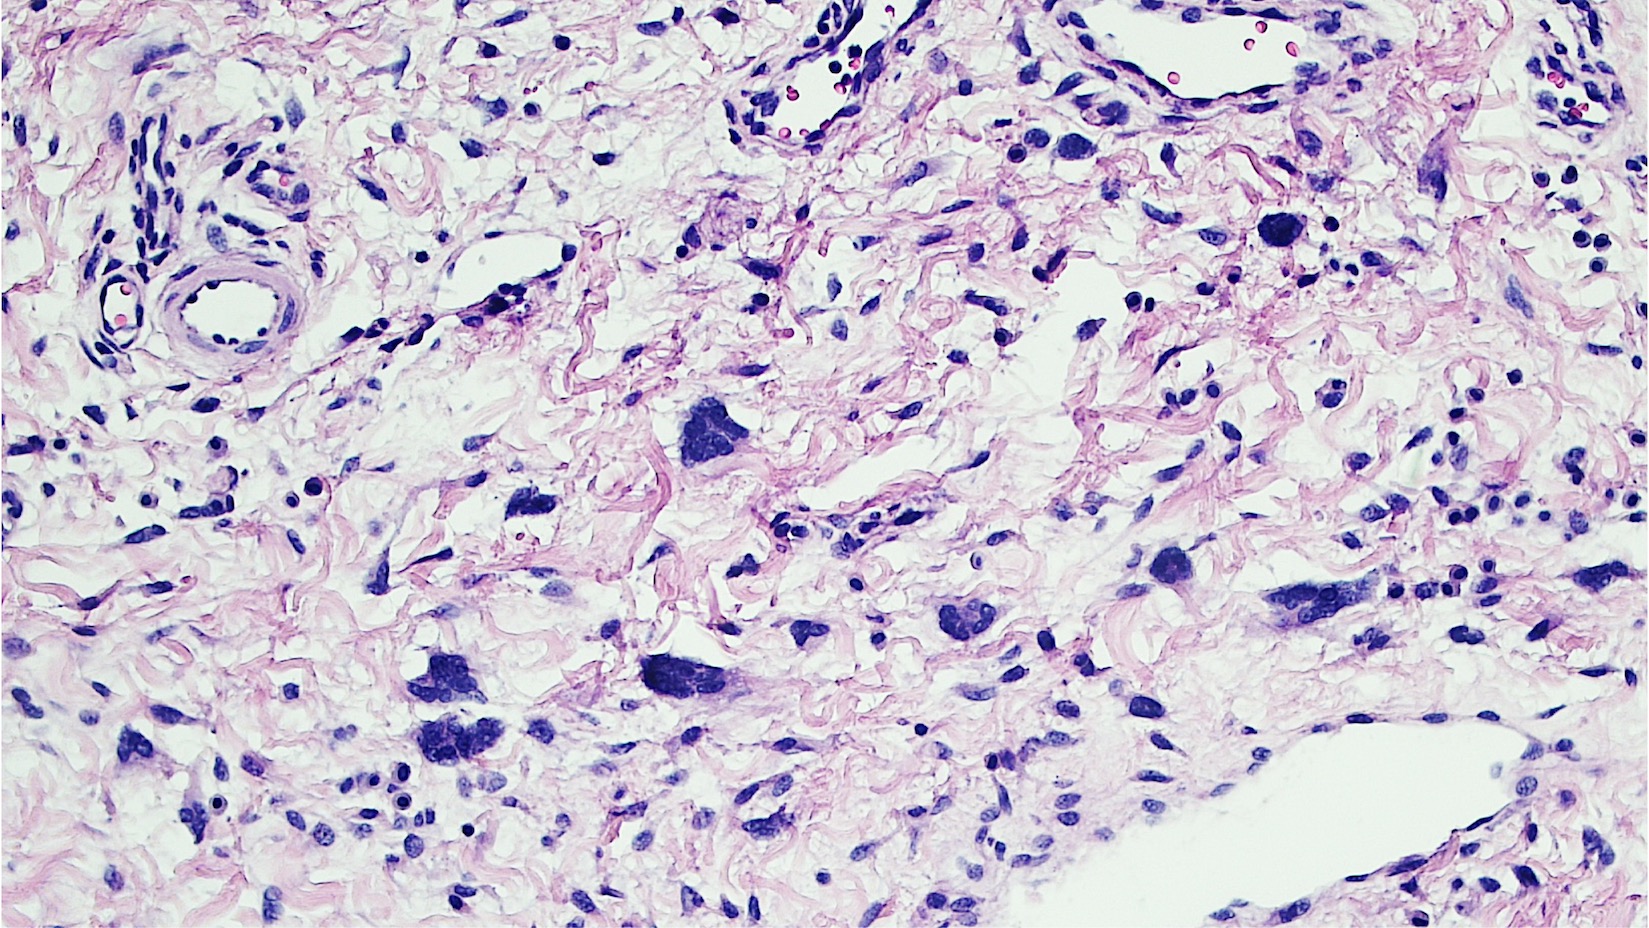

Microscopic (histologic) description

- Polypoid and noncircumscribed, extending to the epithelial / subepithelial interface (J Low Genit Tract Dis 2011;15:69, Am J Surg Pathol 2000;24:231)

- 2 stromal cellularity variants: hypocellular form (spindle cells set within a loose collagenous myxoid-like stroma) or hypercellular variant (exhibits marked nuclear pleomorphism and frequent mitoses, including atypical forms), especially during pregnancy, therefore mimicking leiomyosarcoma or rhabdomyosarcoma (Am J Surg Pathol 2000;24:231)

- Stellate cells should not be interpreted as sarcoma (J Low Genit Tract Dis 2011;15:134)

- Commonly found around blood vessels or near the epidermal stromal interface

Microscopic (histologic) images